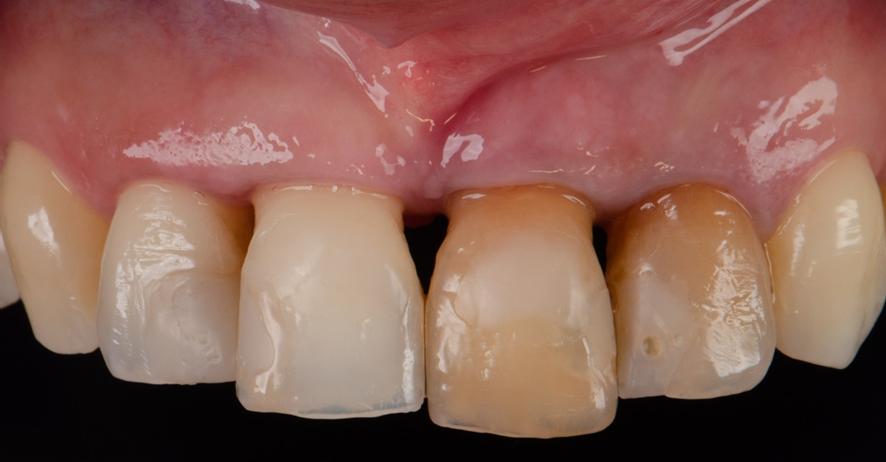

Foi então feito uma ROG (Extra Graft®) na região de GAP entre o implante e o osso alveolar, e confeccionado um cicatrizador personalizado sobre um pilar provisório, para manutenção do arcabouço gengival.

Uma provisória ferulizada foi então instalada, presa aos dentes adjacentes.